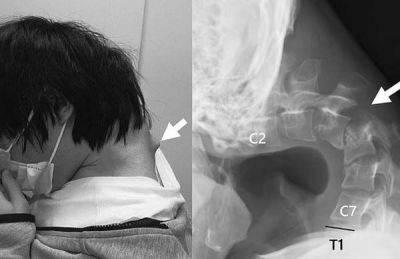

스스로 머리를 들어 올릴 수 없을 정도로 목뼈가 꺾이는 이른바 '머리떨굼 증후군' 진단을 받은 일본 20대 남성의 사연이 알려져 충격을 던졌다. 이 남성은 10대 초반부터 하루에 몇 시간씩 스마트폰 게임을 한 것으로 알려졌다.

의료진은 "고개를 숙인 채 오랜 시간 스마트폰 게임을 하면서 목의 척추뼈가 탈구(뼈가 제자리를 이탈하는 현상)됐다"며 "환자의 목 뒷부분에 흉터처럼 혹이 튀어나왔는데, 비정상적인 자세 때문에 척추뼈가 극도로 늘어난 결과"라고 말했다.

![매일 장시간 스마트폰 게임을 한 결과 목이 꺾이는 ‘머리떨굼 증후군’에 걸린 남성의 엑스레이 사진 [이미지 출처=사이언스 다이렉트 캡처]](https://img1.daumcdn.net/thumb/R658x0.q70/?fname=https://t1.daumcdn.net/news/202505/17/akn/20250517183011398mcjg.jpg)

이에 의료진은 우선 목을 고정하는 의료 기기를 이용해 교정을 시도했다. 그러나 남성이 감각 이상을 호소하면서 결국 목뼈에 나사와 금속 막대를 삽입하는 수술을 진행했다.

수술 후 6개월 만에 이 남성은 머리를 수평으로 유지할 수 있게 됐고, 1년 뒤 추적 검사에서 머리떨굼 증후군 증상이 재발하지 않은 것이 확인돼 일상으로 돌아올 수 있었다.